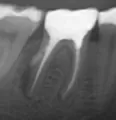

В десне более 6 лет назад была обнаружена гранулема, кроме шишки она ничем себя не проявляла. Зуб залечили, поставили пломбу и сказали,что если шишка не беспокоит, то и делать ничего не нужно. После перенесенной простуды в настоящее время появился гнойный прыщик, скорее всего свищ, но и сейчас зуб особо не беспокоит, иногда пульсирует.

Некачественное лечение и безграмотность в области эндодонтии врачей, ранее лечивших данный зуб, скорее всего привело к потере зуба. Свищ говорит об обширном воспалительном процессе на верхушках корней данного зуба. Болеть зуб не будет пока имеется отток (свищ) . Обратитесь не медля к врачу , в любом случае, будет это удаление или лечение, вмешательство необходимо экстренное, не надо доводить до обострения.